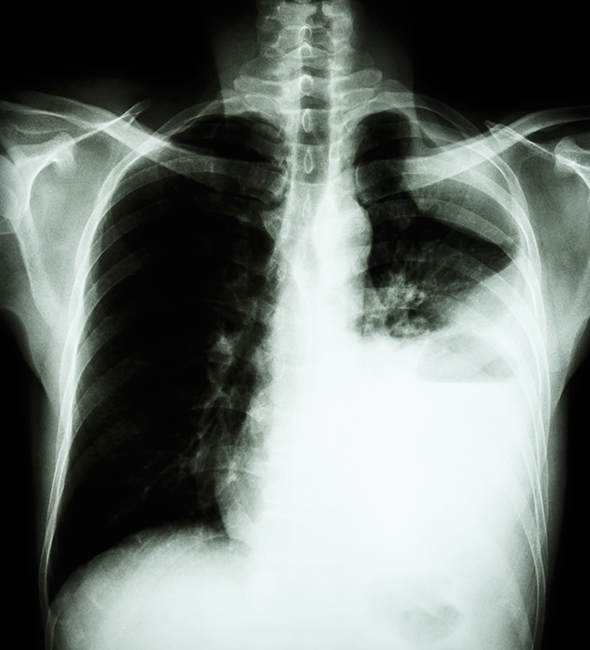

Cuando se inhalan fibras de amianto, éstas pueden alojarse en los pulmones o traspasar las membranas y alcanzar y depositarse en otras partes de cuerpo, causando graves enfermedades como la asbestosis, cánceres de pulmón o de laringe y los mesoteliomas.

Las enfermedades profesionales causadas por el amianto tienen en común la gravedad y el largo período de latencia (algunas de ellas de hasta 40 años), por lo que los efectos a la salud de la exposición al amianto pueden ocurrir años después del inicio de la exposición.

Las enfermedades profesionales causadas por el amianto se encuentran recogidas en el R.D. 1299/2006, de 10 de noviembre, por el que se aprueba el cuadro de enfermedades profesionales en el sistema de la Seguridad Social y se establecen criterios para su notificación y registro:

Además, hay que destacar el efecto sinérgico que produce el tabaco, aumentando la probabilidad de sufrir estas enfermedades, en algunos casos hasta el 50%.

El artículo 16 del R.D. 396/2006 establece que el empresario garantizará una vigilancia adecuada y específica de la salud de los trabajadores expuestos a amianto. El Protocolo de Vigilancia Sanitaria Específica de Amianto se aplica tanto a trabajadores expuestos como a trabajadores post-expuestos, siendo estos últimos, personas que por cualquier circunstancia no trabajan actualmente con amianto pero sí lo han hecho en el pasado (jubilación, cambio de empresa o cambio de tareas dentro de la empresa).